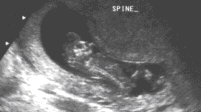

На ультразвуке, черепная коробка симметрично отсутствует. Рудиментарная мозговая ткань покрыта мембраной, а не костью (рис 1-2). Она, как было замечено, выступает над основанием черепа уже вначале второго триместра, и постепенно дегенерирует, пока наконец изображение головы полностью сглаживается позади лицевых структур. Внешний вид лица приобретает подобие лягушки с «выпученными» глазными яблоками (рис 3,4). Сопутствующее многоводие обычно развивается во втором триместре из-за отсутствия или неэффективного эмбрионального глотания (рис. 3). Часто наблюдается повышенная активность эмбриона. Рис.1-4. Сонографические ловушки в диагнозе анэнцефалии обычно возникают вокруг трудностей в визуализации при головном предлежании с глубоким положением головы. Дифференцирование анэнцефалии от серьезной микроцефалии или большого энцефалоцеле может также быть трудно, но при этих состояниях свод черепа всегда присутствует. Связанные с амнионом синдромы, ассоциированные с разрушением головного мозга, могут также имитировать анэнцефалию. Наконец, неопытный сонографист может путать мембрану с нормальным сводом черепа в раннем втором триместре. Поэтому, идентификация эмбриональной головы не исключает анэнцефалии.